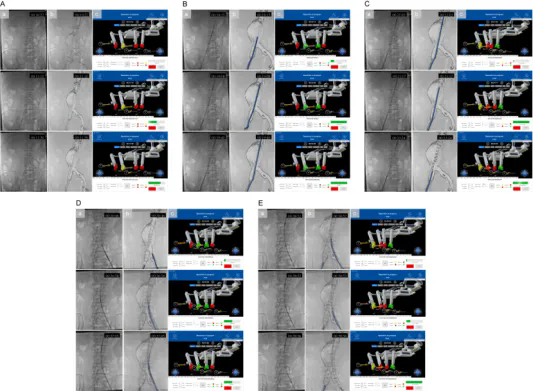

作为国家“新一代人工智能”专项承担单位,奥朋医疗凭借近百项国内外核心专利技术储备,此次手术实现四大核心突破,树立行业新标杆: 1.全球首创 EVAR 全流程自动化 首次实现从导丝推进、导管输送到支架精准释放的全环节无人干预操作,彻底突破现有机器人“手控为主、半自动为辅”的技术局限,将血管介入手术的自动化程度提升至全新高度。 2.独创“手术步骤参数化”新范式: 基于奥朋医疗自主研发的 Endosize软件,通过术前 CTA影像3D重建与精准建模,将复杂EVAR手术拆解为可编程、可重复的标准单元,自动生成器械运动参数,推动血管介入治疗从“经验依赖”向“标准量化”转型。 3.高兼容+多重安全保障体系: 系统兼容市售主流导丝、导管及支架等常规耗材,解决了传统机器人“耗材适配性差”的行业痛点;内置2N力反馈阈值自动暂停机制,搭配人机协同检查点、物理+虚拟双急停按钮,实现“精准操作+安全可控”的双重保障。 4.构建开放式智能介入平台: 该平台依托奥朋医疗“血管介入领域达芬奇”的技术定位,可无缝拓展至冠脉、神经、外周等8大介入领域,为未来融合AI自主导航、5G远程手术奠定坚实基础,彰显强大技术延展性。 图示:基于3D打印血管模型的体外验证实验。图中展示了支架植入的关键步骤,包括主体支架输送、精确定位、释放以及分支支架植入。本图包含三个视角:(A) 聚焦于血管模型的近景视图;(B) 展示整个实验环境的广角视图;(C) 操作台监视器界面的截图。 图示:自动化机器人辅助EVAR人体验证的支架植入过程。在导入超硬导丝后(见图4A),首先以10 mm/s的速度快速将支架输送系统推进至目标位置附近,随后以1 mm/s的慢速进行微调,最终实现支架在目标点的精准定位(见图4B)。随后进行支架释放,并通过逆时针旋转释放手柄5400°(转速90°/s)完成裸段释放过程(见图4C)。在人工完成对侧短腿超选并建立超硬导丝通道后,分支支架以与主体支架相同的方式输送并释放(见图4D、E)。 破解行业痛点,奥朋医疗给出中国方案 血管介入手术机器人虽已在临床展现出“提升精度、减少辐射”的显著优势,但长期面临两大瓶颈:一是难以兼容常规耗材,无法满足EVAR等复杂多器械协同手术需求;二是自动化局限于单一步骤,难以实现全流程闭环操作。而腹主动脉瘤作为“人体定时炸弹”,其主流治疗方式EVAR手术对操作精度、流程连贯性要求极高,传统人工手术不仅术者面临高辐射风险,还存在因经验差异导致的诊疗同质化难题。 在此背景下,奥朋医疗深耕“医工融合”创新理念,针对性研发全自动、高兼容、安全可控的主从式血管介入手术机器人平台,精准破解行业痛点,为复杂血管介入手术提供了兼具临床适配性与技术先进性的中国解决方案。 硬核技术支撑,临床数据彰显实力 本次研究采用奥朋医疗自主研发的主从式机器人平台,集成多自由度机械臂与高精度驱动模块,通过“术前精准规划—术中自动执行—阶段协同确认”的闭环流程,实现毫米级操作精度。研究先经3D打印血管模型充分验证,再成功应用于4例肾下型腹主动脉瘤患者,取得卓越临床成果: • 手术成功率100%:4例患者均顺利完成全流程自动化手术,术后CTA证实支架定位精准,无内漏及相关并发症; • 诊疗效率大幅提升:平均手术时间仅110分钟,透视时间19分钟,较传统手术显著缩短; • 辐射防护成效显著:术者辐射剂量低至4mGy,较传统手术减少90%以上,从根本上保障医护人员职业健康; • 稳定性全面验证:所有自动化步骤均未发生意外中断,无需人工接管,充分证明系统的临床可靠性。 (图示:血管介入手术机器人的组成与工作原理。(A) 血管介入手术机器人整体示意图。手术过程中,术者坐于操作台前(位于铅屏后方),远程控制终端机械单元;(B) 操作台的显示界面与功能说明;(C) 自动化机器人辅助EVAR手术的执行流程图。) (图示:基于Endosize软件的EVAR术前规划。图中展示了中心线及关键定位点。导丝的移动距离为从Pl点至P1点;导管的移动距离为从Pr点至P2点;主体支架的移动距离为从Pr点至P3a点;分支支架的移动距离为从Pl点至P4a点。) 引领行业变革,绘就智能介入新蓝图 作为当前全球唯一实现冠脉、外周、主动脉介入手术同步临床推进的企业,奥朋医疗此次突破性成果,不仅验证了全自动化EVAR手术的临床可行性,更通过标准化范式构建,为缩小不同层级医疗机构技术差距、提升基层诊疗同质化水平提供了有效路径。 未来,奥朋医疗将持续深化“精准、智能、微创”的技术理念,进一步拓展该平台至复杂主动脉病变、神经血管介入等更多场景,并融合AI实时导航、5G远程手术等前沿技术,推动血管介入手术向“自主决策、全域覆盖、优质资源下沉”的更高阶段迈进。正如奥朋医疗的发展愿景——致力于成为“血管介入领域的达芬奇”,以中国智造打破国际技术垄断,为全球患者带来更安全、更高效、更可及的医疗服务。